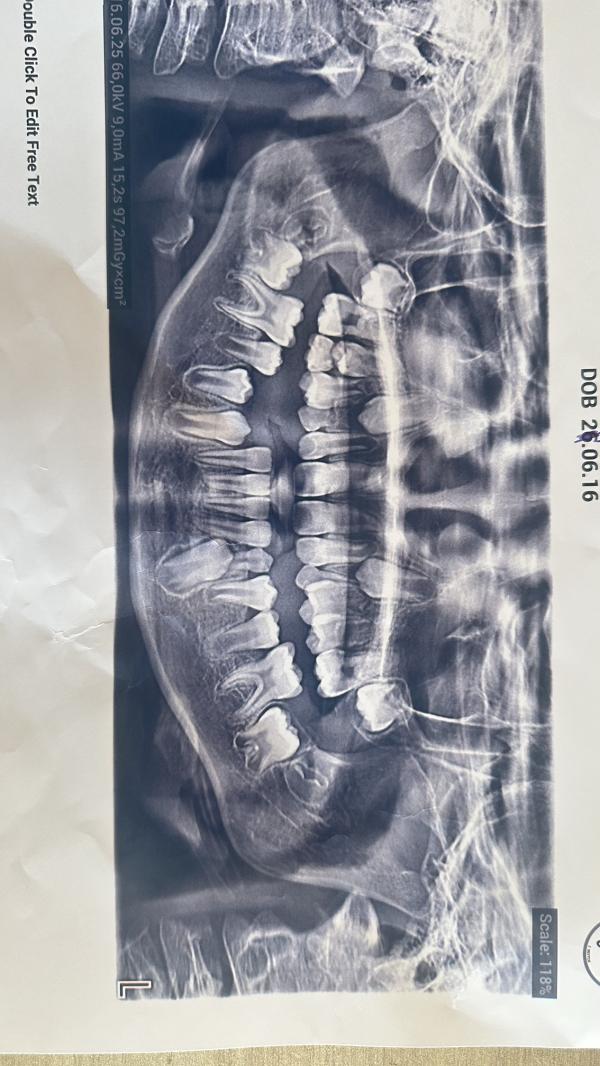

🔸прилагаю снимок зубов

Осмотрев сына, стоматолог сказала что у сына верхняя челюсть чуть-чуть сдвинута вперед и спросила хотите ли вы ставить пластины?

На верхней не хватает места для постоянных